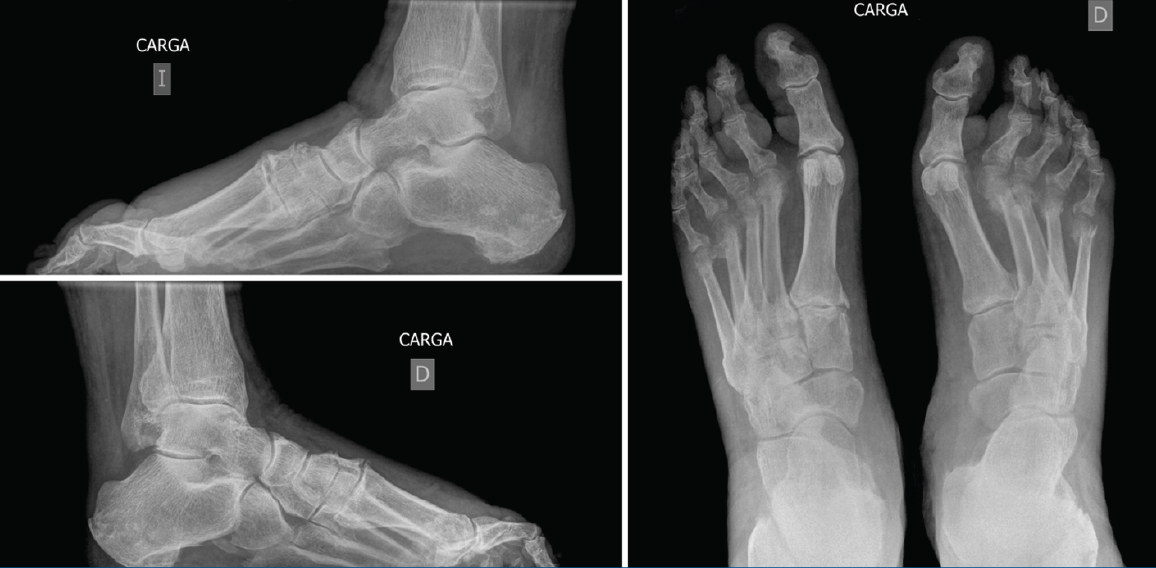

El tiempo medio de curación de la úlcera tras la intervención quirúrgica fue de 3,3 semanas (rango: 2-5 semanas) con una tasa de curación del 100% (Figuras 1 y 2). En los controles radiográficos postoperatorios se objetivó una consolidación ósea de la osteotomía en el 100% de los casos con un ascenso de la cabeza y un acortamiento medio de 2,7 mm (Figuras 3 y 4). Sin embargo, dado que 6 de los 15 pacientes incluidos en el estudio presentaban amputaciones metatarsianas previas, la fórmula metatarsiana postoperatoria no pudo ser objeto de nuestro estudio.

Figura 4. Imágenes radiológicas postoperatorias en carga. Se visualiza la consolidación de la osteotomía del 2.º al 5.º metatarsianos con acortamiento y elevación de la cabeza.